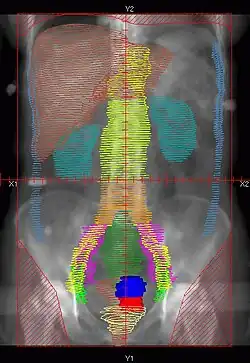

- There are multiple techniques, but typically Whole Abdomen RT is given to 22.5-25 Gy, followed by boost to PA LNs and whole pelvis to 45-50.4 Gy

- Dose: 22.5-25Gy in 130-150cGy/fx.

- Simulation: Supine with Alpha cradle.

- Fields: AP/PA single fields or 4-field technique

- Blocks:

- Kidneys – 50% transmission block or block after 15Gy.

- Liver – Block at 25Gy. Block not used by some institutions.

![]() |

Example of a AP whole abdomen/pelvis radiation therapy treatment field used at Tufts/Brown residency program. Actual patient contours should guide field design.